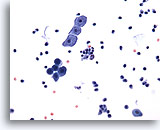

Urine prélevée à partir d’une vessie iléale, négatif

Les lavages d’urine prélevée à partir d’une vessie iléale contiennent des cellules glandulaires bénignes.

40x